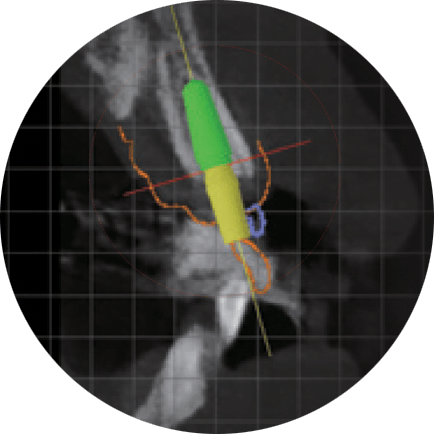

Virtuali chirurgija pasinaudojus skaitmenine diagnostikos programa

Siekiant kuo tikslesnės ir mažiau invazyvios chirurgijos, implantų pozicija, anguliacija, ilgis ir diametras yra pateikiami jau prieš implantaciją.

Siekiant išvengti tokių komplikacijų: apatinio žandikaulio nervo sužalojimas, ančio dugno perforacija, – chirurginis gidas yra vienintelis saugus ir patikimas sprendimas šioje situacijoje.

Virtuali chirurgija